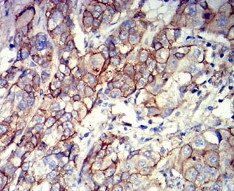

CD166 Mouse Monoclonal antibody[3F1]

This gene encodes activated leukocyte cell adhesion molecule (ALCAM), also known as CD166 (cluster of differentiation 166), which is a member of a subfamily of immunoglobulin receptors with five immunoglobulin-like domains (VVC2C2C2) in the extracellular domain. This protein binds to T-cell differentiation antigene CD6, and is implicated in the processes of cell adhesion and migration. Multiple alternatively spliced transcript variants encoding different isoforms have been found.

IHC    1/200 - 1/1000